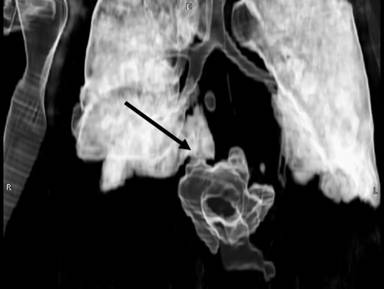

A 40-year-old woman had been admitted for an endoscopic drainage of pseudocyst that developed secondary to gallstone-induced pancreatitis treated elsewhere. The procedure needed to be postponed due to development of a large pulmonary embolus for which the patient was anti-coagulated. As the pseudocyst decreased in size (5 cm diameter) on CT imaging, no drainage was attempted on that admission. Four months later she was re-admitted as an emergency with acute upper abdominal pain and vomiting. On arrival, the patient was unwell, dehydrated and tachycardic. The clinical diagnosis of pancreatitis was confirmed by the raised serum amylase of 203 U/L (reference range: 0-135 U/L). The APACHE II score was 11 (adjusted predicted death rate of 19.6%). Within 12 hours she rapidly deteriorated, developed type I respiratory failure and required respiratory support. The contrast CT revealed that the known pseudocyst had increased in size, measuring 11.7x5.0 cm with features of pancreatic necrosis (Figure 1) and large bilateral pleural effusions. It extended into the posterior mediastineum around the oesophagus. Bilateral chest drains were inserted and ionotropic cardiac support implemented. At this stage her APACHE II score was calculated at 20 (adjusted predicted death rate of 47.6%). Since the patient continued to deteriorate, endotracheal ventilation became necessary. Immediately after insertion of the endotracheal tube, 2 L of amylase rich fluid (26,562 U/L) spontaneously drained via the tube. The diagnosis of a pancreaticobronchial fistula was confirmed on the repeated contrast CT (7 days after the admission), which showed a large amount of gas inside the cyst and evidence of fistulation into the right lower lobe bronchi (Figures 2 and 3). The pseudocyst was drained percutaneously under the CT guidance via the transgastric route and the pleural collections by bilateral chest tubes (amylase: 13,995 U/L). Subsequent tubogram and bronchoscopy did not confirm the fistulous connection with the bronchial tree. Subsequently, 16 days following the admission, due to progressive deterioration, the patient underwent an open pancreatic necrosectomy. Intraoperatively, the pancreatic collection was tracking cranially towards the diaphragm. With every lung inflation by the ventilator air was seen to escape from the peripancreatic collection indicating a communication with the airway. Therefore, following debridement of the peripancreatic tissues, an underwater-seal drain was inserted into the cavity. Four days after the necrosectomy the woman was weaned off the ventilator and the air leak in the under water seal drain ceased within the next 5 days. The abdominal drains were removed on the 11th postoperative day. The patient returned to the surgical ward after 4 weeks of intensive therapy unit (APACHE II score 1, adjusted predicted death rate 5.4%) and following a prolonged period of convalescence, was discharged home 2 months later. The open drainage of the cyst and the pleural collections combined with supportive measures such as intravenous octreotide infusion and parental nutrition (L-alanyl-L-glutamine-supplemented parental nutrition) for 24 days resulted in the successful recovery.

Figure 3. 3-dimentional reconstruction of the pancreaticobronchial fistula on the CT 7 days post admission (see arrow). |